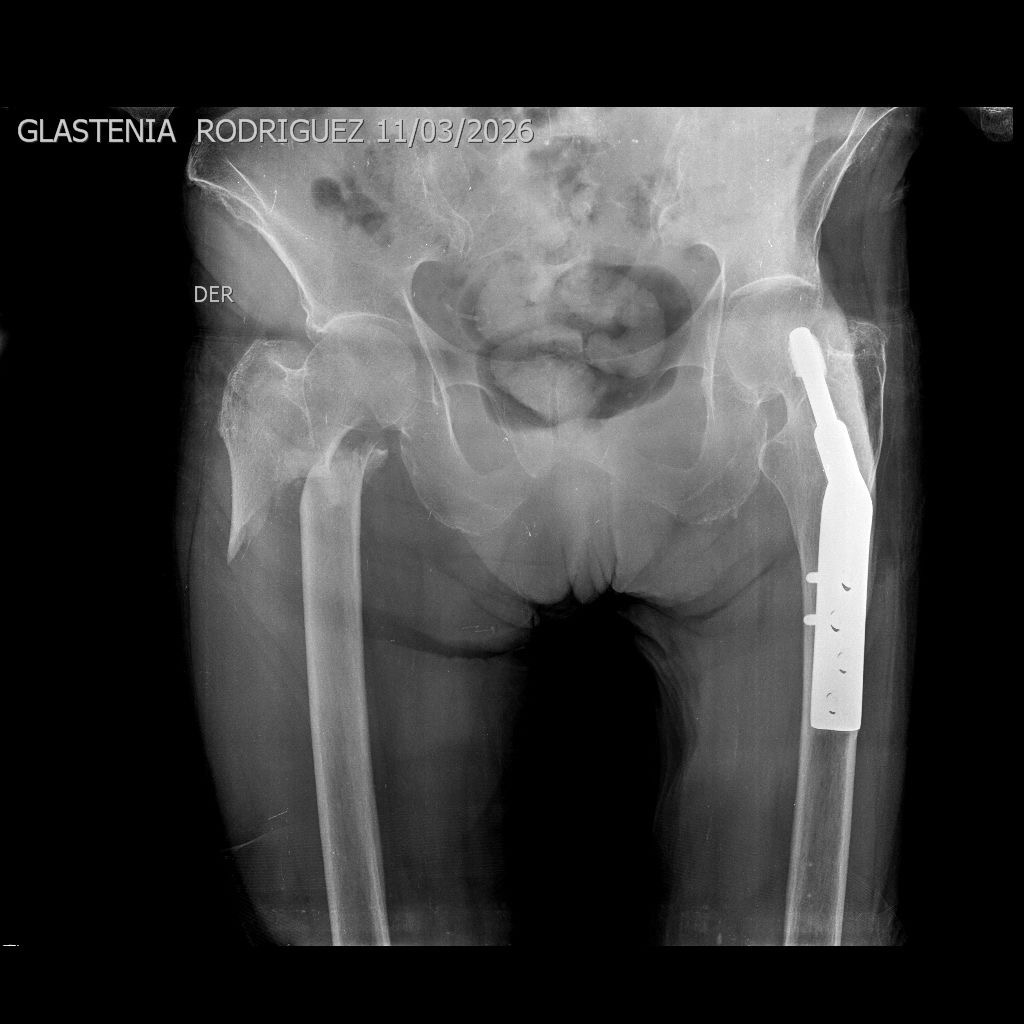

Mi tía sufrió una caída y actualmente presenta una fractura desplazada en el fémur, cerca de la cadera. Debido a la gravedad de la lesión, el hueso perdió su alineación normal y requiere intervención quirúrgica para estabilizarlo, y así permitir su correcta recuperación.